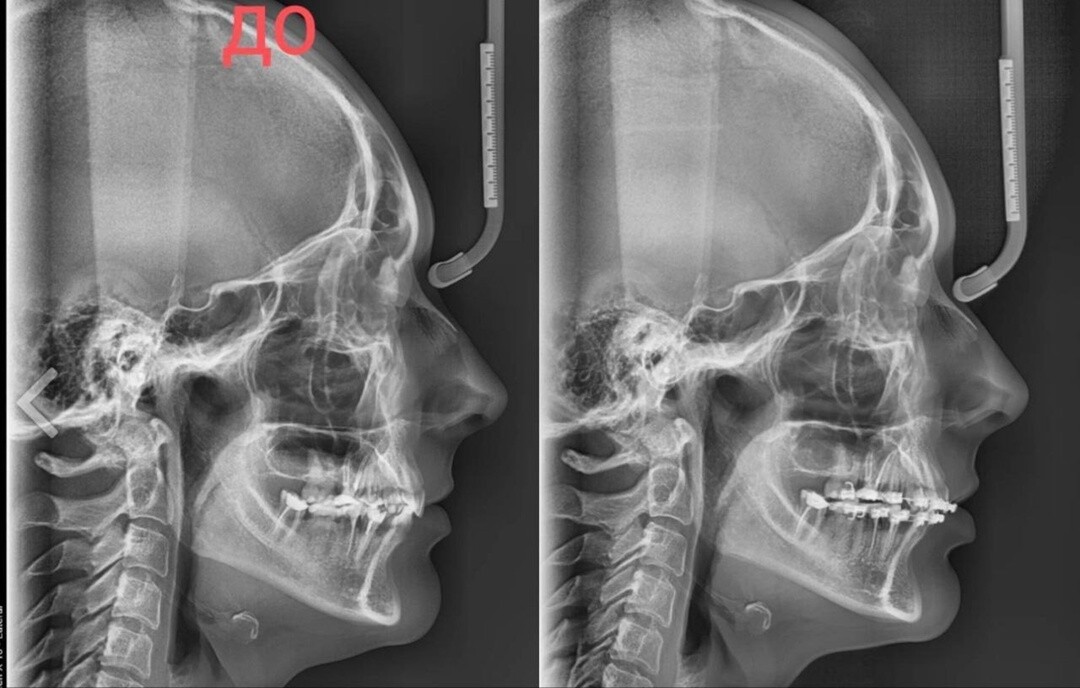

Но интересно другое. Там есть снимки черепа и можно сравнить. Листай карусель👇

Отметила на них самое очевидное.

И хотя такие исследования надо делать в программе и по КТ, но даже так несколько моментов видны невооруженным глазом.

Вот все эти расстояния, отмеченные красным - увеличились, и изменился наклон окклюзионной плоскости. И шея пошла вперед.